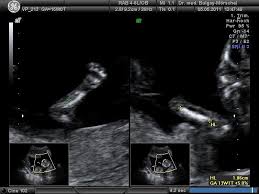

Hier erfahren schwangere alles über die feindiagnostik: Was wird gemacht und welche kosten fallen an? Was passiert bei der feindiagnostik? Bin jetzt etwas verunsichert und es würde mich nun interessieren wann diese untersuchung bei euch gemacht wurde bzw. In solchen fällen wird häufig eine feindiagnostik angeraten. Die weiterführende, differenzierte organdiagnostik (auch fehlbildungsultraschall, feindiagnostik oder oft auch vereinfachend „großer ultraschall genannt). Der altersdurchschnitt der werdenden mütter steigt. Wann sollte das organscreening gemacht werden? Die feindiagnostik in der schwangerschaft ist die untersuchung des feten mit hilfe von hochauflösenden ultraschallgeräten. Ab wann ist diese feindiagnostik eigentlich möglich? Dann sind sie bei dres. Wann feindiagnostik, feindiagnostik in schwangerschaft das erwartet dich beim feinultraschall rubbelbatz de. Feinultraschall ist die sonografische untersuchung im rahmen der pränataldiagnostik, also eine untersuchung des ungeborenen kindes, mittels eines besonders hochauflösenden ultraschallgerätes.

Deutschland europa fernreisen hoteltipps reisenews wellnessurlaub kreuzfahrten freizeitparks reisevideos stauprognose. Wann ist eine fetale herzdiagnostik sinnvoll? Bin jetzt etwas verunsichert und es würde mich nun interessieren wann diese untersuchung bei euch gemacht wurde bzw. Wann kann eine fetale echokardiografie durchgeführt werden? Ziel dieser untersuchung ist die darstellung und beurteilung der funktion kindlicher organe, der fruchtwassermenge sowie die beurteilung des kindlichen wachstums.

Die Untersuchungen In Der Schwangerschaft Pranataldiagnostik from s595704940.online.de Wann ist eine fetale herzdiagnostik sinnvoll? Synonym werden die ausdrücke sonografische feindiagnostik. Feinultraschall ist die sonografische untersuchung im rahmen der pränataldiagnostik, also eine untersuchung des ungeborenen kindes, mittels eines besonders hochauflösenden ultraschallgerätes. Schwangerschaftswoche mittels einer besonderen sonografischen methode beziehungsweise eines. Wann kann eine fetale echokardiografie durchgeführt werden? Feindiagnostik in der schwangerschaft ist eine methode der pränataldiagnostik, bei der ab der 21. Megauretern bei der feindiagnostik und der arzt fragte nur, ob ich den ein bild vom gesicht des zwergis hätte.und da wurde halt mehr durch zufall festgestellt. Ab wann kann man die feindiagnostik machen.